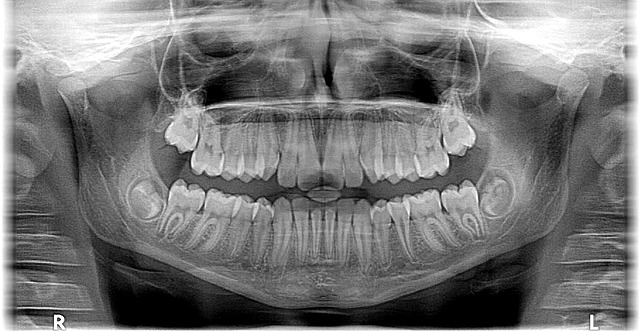

Additionally, our commitment to modern technology includes utilizing digital imaging and advanced diagnostic tools. These enable us to provide more accurate diagnoses and develop personalized treatment plans. For example, 3D imaging allows for a detailed view of dental structures, making it easier to plan complex procedures like braces or implants. By embracing these innovations, we can offer more efficient, comfortable, and effective care in our McAllen office. Don’t miss out—schedule an appointment now by dialing 956-686-5000 to experience the difference modern technology makes in dental care. Call our office at 956-686-5000 for more information or to book your visit.